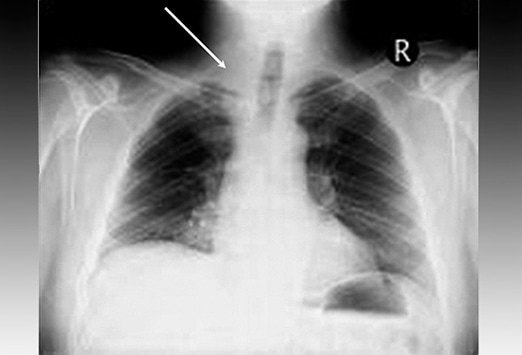

Рентгеновские снимки опухоли Панкоста